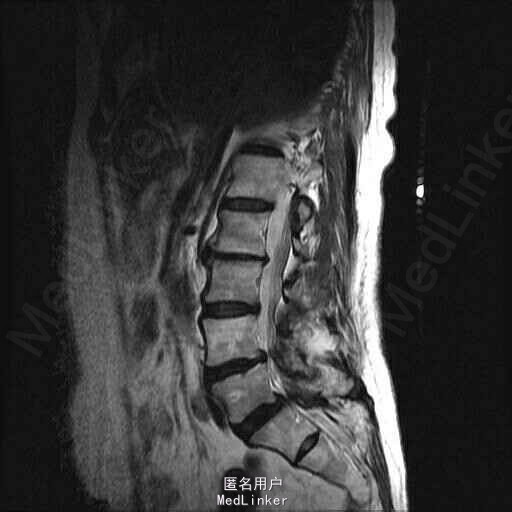

主诉:右下肢麻木伴驼背11年余 病史:患者女性,64岁,11年前无明显诱因出现右下肢疼痛,休息后好转。未予重视,后出现右下肢麻木感,逐渐小狐仙右臀部坚硬,驼背,伴跛行。常感双腿酸胀,腰部疼痛。自行步行距离小于200米,即会发生右下肢僵硬,麻木疼痛。X线检查示腰椎侧弯

查体:脊柱侧弯,上肢无麻木,疼痛感觉异常,腰部右侧疼痛,右下肢及右臀部疼痛,麻木感。双侧肌力及肌张力可,膝腱反射(+),踝反射(+),病理征(—),直腿抬高试验。右侧40度,左侧55度。 辅助检查:腰椎x线片:腰椎侧弯,腰椎退行性改变,L5椎体略行前滑脱 脊柱全长:胸腰段呈S形,L5椎体向前滑脱,L3椎体略变扁,颈胸腰椎退行性改变 MRI:脊柱侧弯,L2-3,L3-L4,L4-L5,L5-S1椎间盘突出,相应节段椎管狭窄

诊断:腰椎侧弯,腰椎椎管狭窄 治疗:手术矫形:早期侧路减压融合,后期再行后路固定。